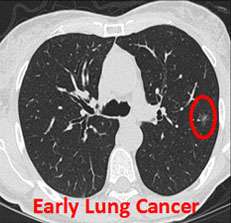

- Early detection of lung cancer

- CT scan